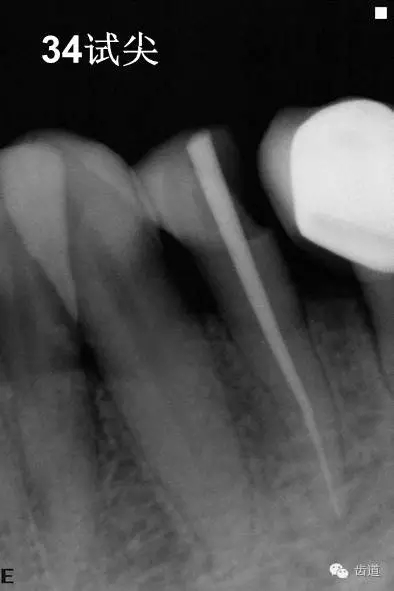

3、34術(shù)前片顯示遠(yuǎn)中面暗影近髓

4、34常規(guī)根管治療。(2013年8月)